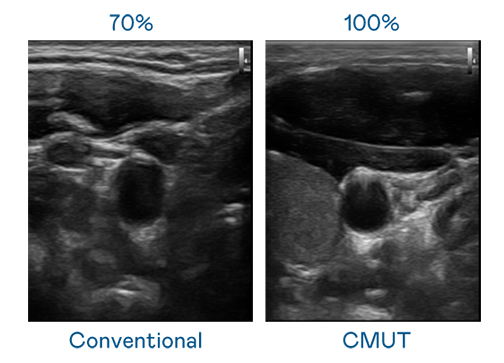

CMUT 技術是一種用電容式微機電元件來產生超音波訊號的技術。與傳統 PZT 壓電式技術相比,CMUT 頻寬增加 30%,更寬頻的超音波訊號讓影像解析度大幅提升,是實現高影像品質醫療超音波掃描、促進精準醫療發展的關鍵技術。

大頻寬帶來超清晰影像

超音波影像的解析度高低,首先取決於探頭能發出的訊號頻寬。九游 CMUT 可提供高清晰的超音波訊號,提供高頻寬、高靈敏度、影像紋理細節更高的超音波影像,協助醫護人員縮短影像判讀時間及利用精準的醫療影像進行診斷。